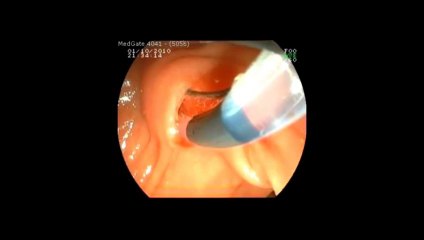

Prof Dr Kayıhan Günay - Polip Çıkarılması

Prof Dr Kayıhan Günay polip çıkarılması.